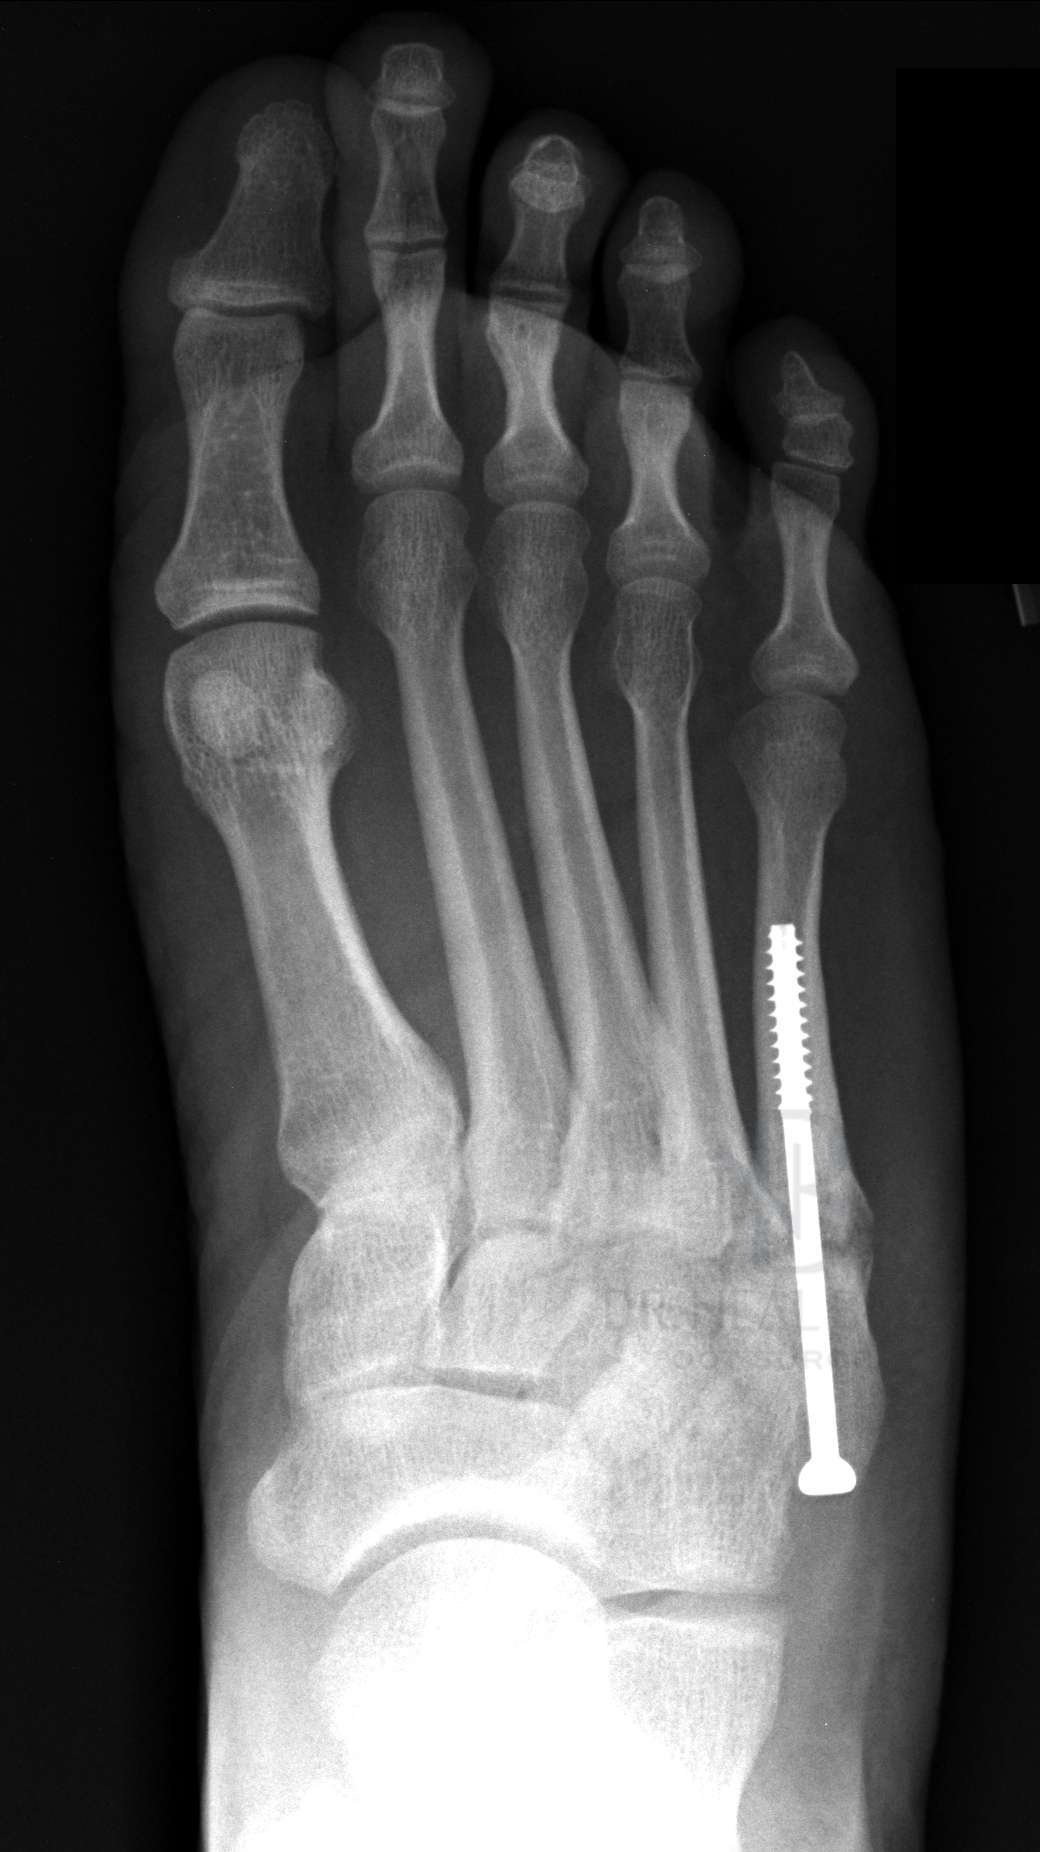

- 수술: 복합 골절이나 압박 골절의 경우에는 핀을 박는 수술이 필요할 수 있습니다.

- 금속판 사용: 뼈가 조각나거나 비스듬하게 부러진 경우에는 금속판을 덧대어 고정하기도 합니다.